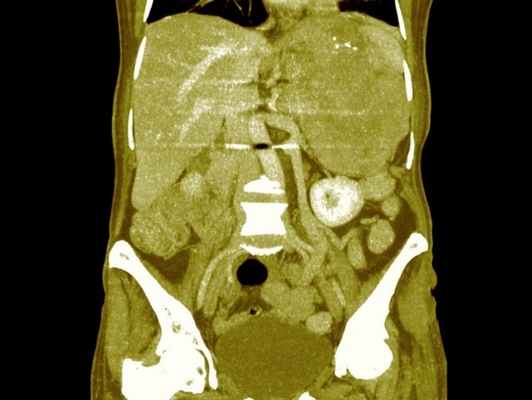

В настоящее время широко используется УЗИ, КТ или МР-томография для выявления расположения опухоли надпочечника, наличия метастазов.

Андростерома гормонально-активная опухоль коры надпочечника, исходящая в основном из ее сетчатой зоны, избыточно выделяющая кортикостероиды, но преимущественно андрогены, и характеризующаяся клинической картиной, сходной с врожденной дисфункцией коры надпочечников . Заболевание может встречаться в любом возрасте у лиц обоего пола. Решающее значение при постановке диагноза андростеромы имеют данные компьютерной томографии надпочечников. Представлен клинический случай, обучающий основам клиники, дифференциальной диагностики и лечения андро-стеромы.

Андростерома - гормонально-активная опухоль коры надпочечника, исходящая в основном из ее сетчатой зоны, избыточно выделяющая кортикостероиды, но преимущественно андрогены, и характеризующаяся клинической картиной, сходной с врожденной дисфункцией коры надпочечников. Заболевание может встречаться в любом возрасте у лиц обоего пола. Решающее значение при постановке диагноза андростеромы имеют данные компьютерной томографии надпочечников. Представлен клинический случай, обучающий основам клиники, дифференциальной диагностики и лечения андро-стеромы.

роме. Иногда появляются отдельные симптомы, характерные для болезни Иценко-Кушинга, что обусловлено гиперпродукцией глюкокортикоидов. С целью визуализации надпочечников используется РКТ, при этом выявляется чаще односторонняя опухоль надпочечника. Данные РКТ имеют решающее значение при постановке диагноза андростеромы. Дифференциальную диагностику следует проводить с двусторонней вирилизирую-щей гиперплазией надпочечников. Для этого проводят пробы с введением АКТГ и дексаметазона. В связи с определенной автономностью опухоли, т. е. независимостью ее функции от регулирующего влияния гипофиза, введение АКТГ и декса-метазона не сопровождается изменением экскреции 17-КС. Рентгенологическое исследование (супраренографию) сочетают с ретроградной или инфузионной пиелографией. Из других заболеваний, сопровождающихся вирилизацией, следует помнить об опухолях яичников, продуцирующих андрогены, адренобластомах. В этих случаях экскреция 17-КС не изменена или умеренно повышена неадекватно степени вирилизации. Методом диагностики служит гинекологический осмотр и рентгенодиагностика (оксипельвиография). Увеличение яичника с одной стороны дает основания подозревать опухоль. Описаны отдельные случаи развития вирильного синдрома на почве

Компьютерная томография — множественные узловатые образования обоих надпочечников. Аденомы. При гистологическом исследовании биоптата — темно-клеточная аденома коры надпочечников с массивными кровоизлияниями. УЗИ матки и придатков — состояние соответствует гипоэстрогении.